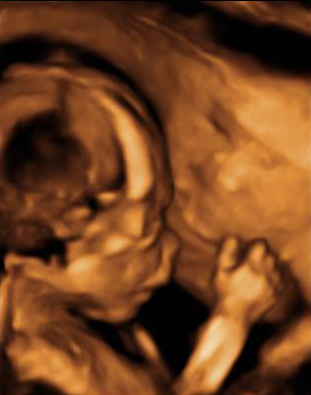

Las ecografías en 2D y en 3D en la semana 20 de embarazo permite diagnosticar algunas malformaciones congénitas fetales, como el labio leporino, que se visualiza en estas imágenes.

Labio leporino (*)

Visualización del mismo caso con ecografía 2D (izquierda) y con ecografía 3D (derecha). La imagen más evidente en la ecografía 3D hace más comprensible para los padres el alcance del problema.

Ecografía Embarazo 2D y 3D Semana 20 - MALFORMACIONES FETALES